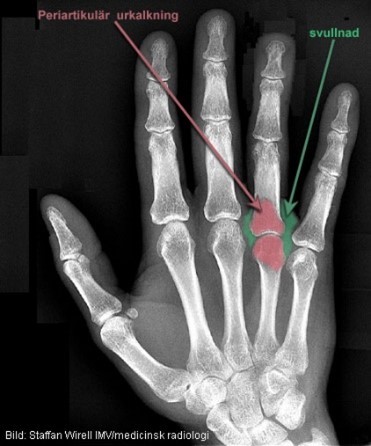

Vad har denna patient troligen drabbats av?

RA

Ses något patologiskt?

Vätska och inflammationsceller ansamlas i synovium och skapar en förtjockad synovialvävnad

Pannus